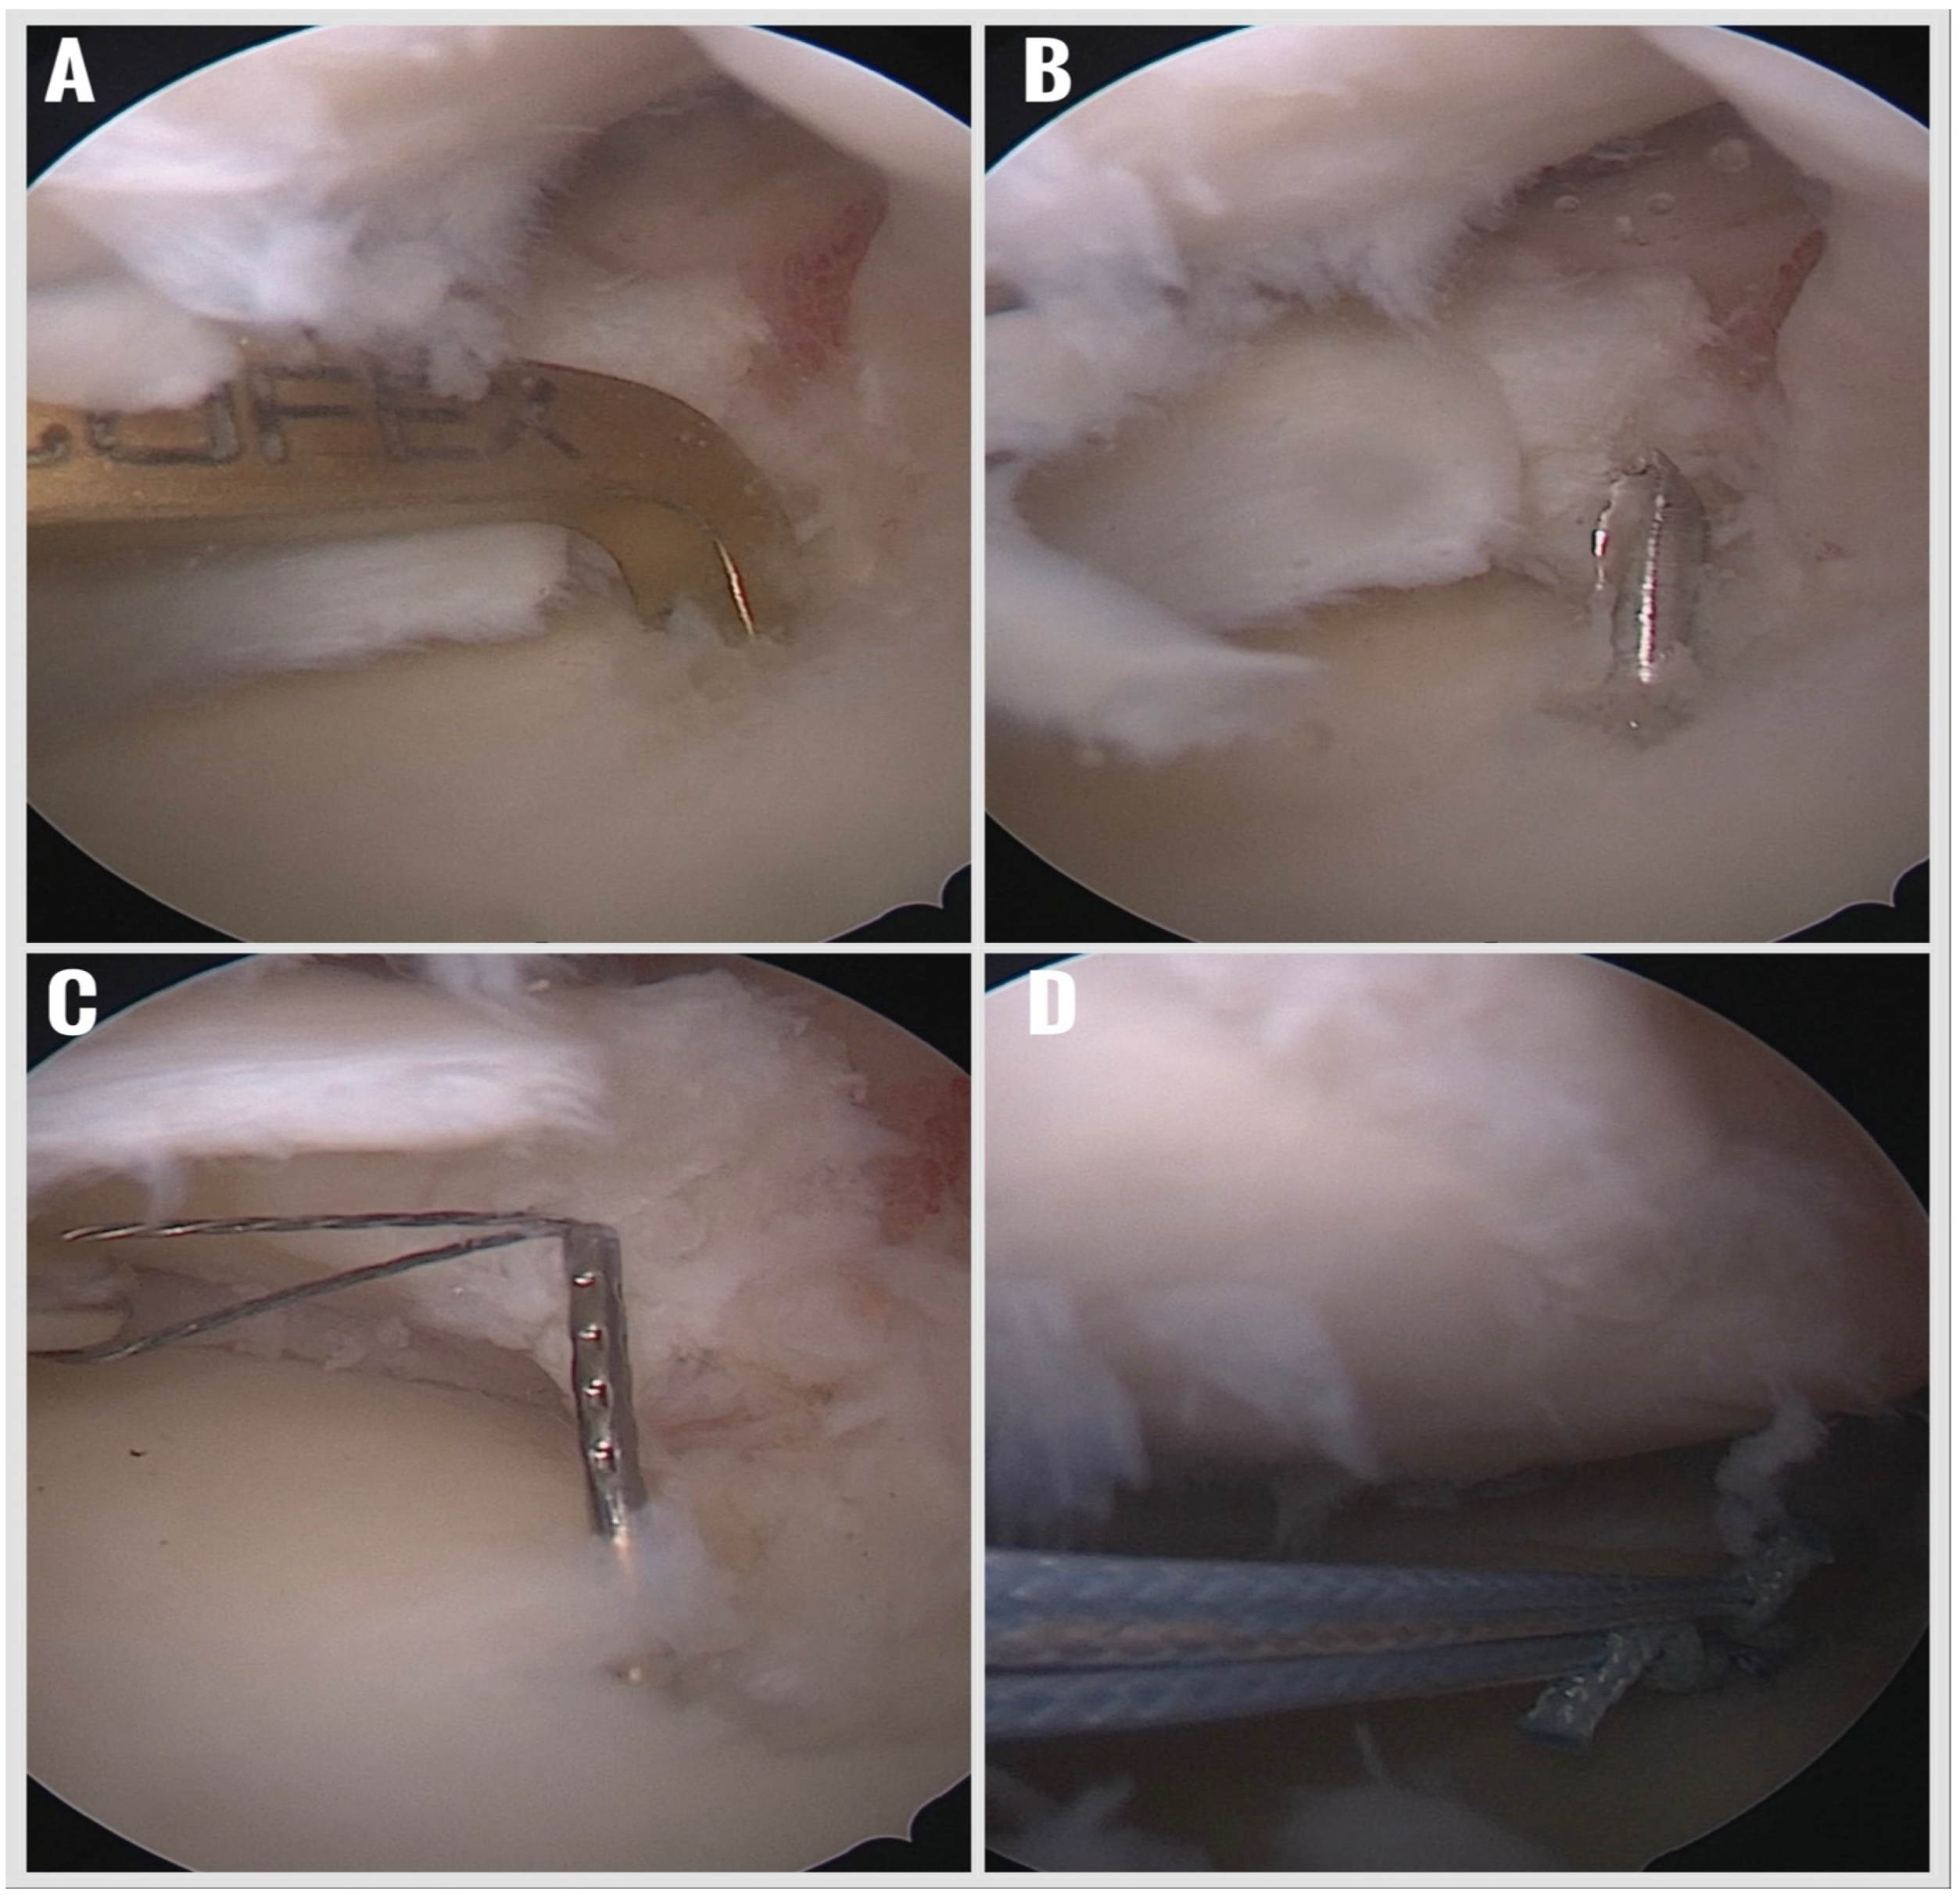

Figure 3. Opening of the tibial tunnel to the previously prepared meniscus attachment area with a 1.8 mm thick K-wire. (A) Positioning the K-wire guide. (B) Opening the tunnel with the K-wire. (C) Pulling the carrier suture into the tunnel with the suture lasso. (D) Pulling the suture anchor into the tunnel.

Creation of a Retrograde Tibial Tunnel:

With the arthroscope switched to the AM portal for improved visualization, a standard ACL tibial aiming guide was introduced through whichever portal was deemed safest for guide placement—typically the AL portal—and positioned precisely at the anatomic root attachment site. A 1.8 mm Kirschner wire was drilled retrogradely from the anteromedial tibial cortex to the prepared meniscal root footprint, creating a tibial tunnel (Figure 3). A shuttle suture was then passed through this tunnel to facilitate subsequent anchor placement.